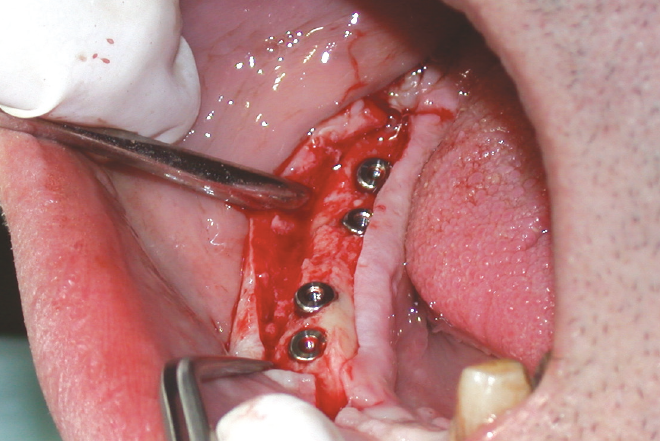

- Figg. 5-10 – Inserimento degli impianti nel settore laterale di sinistra del mascellare superiore

- Fig. 6

- Fig. 7

- Fig. 8

- Fig. 9

- Fig. 10